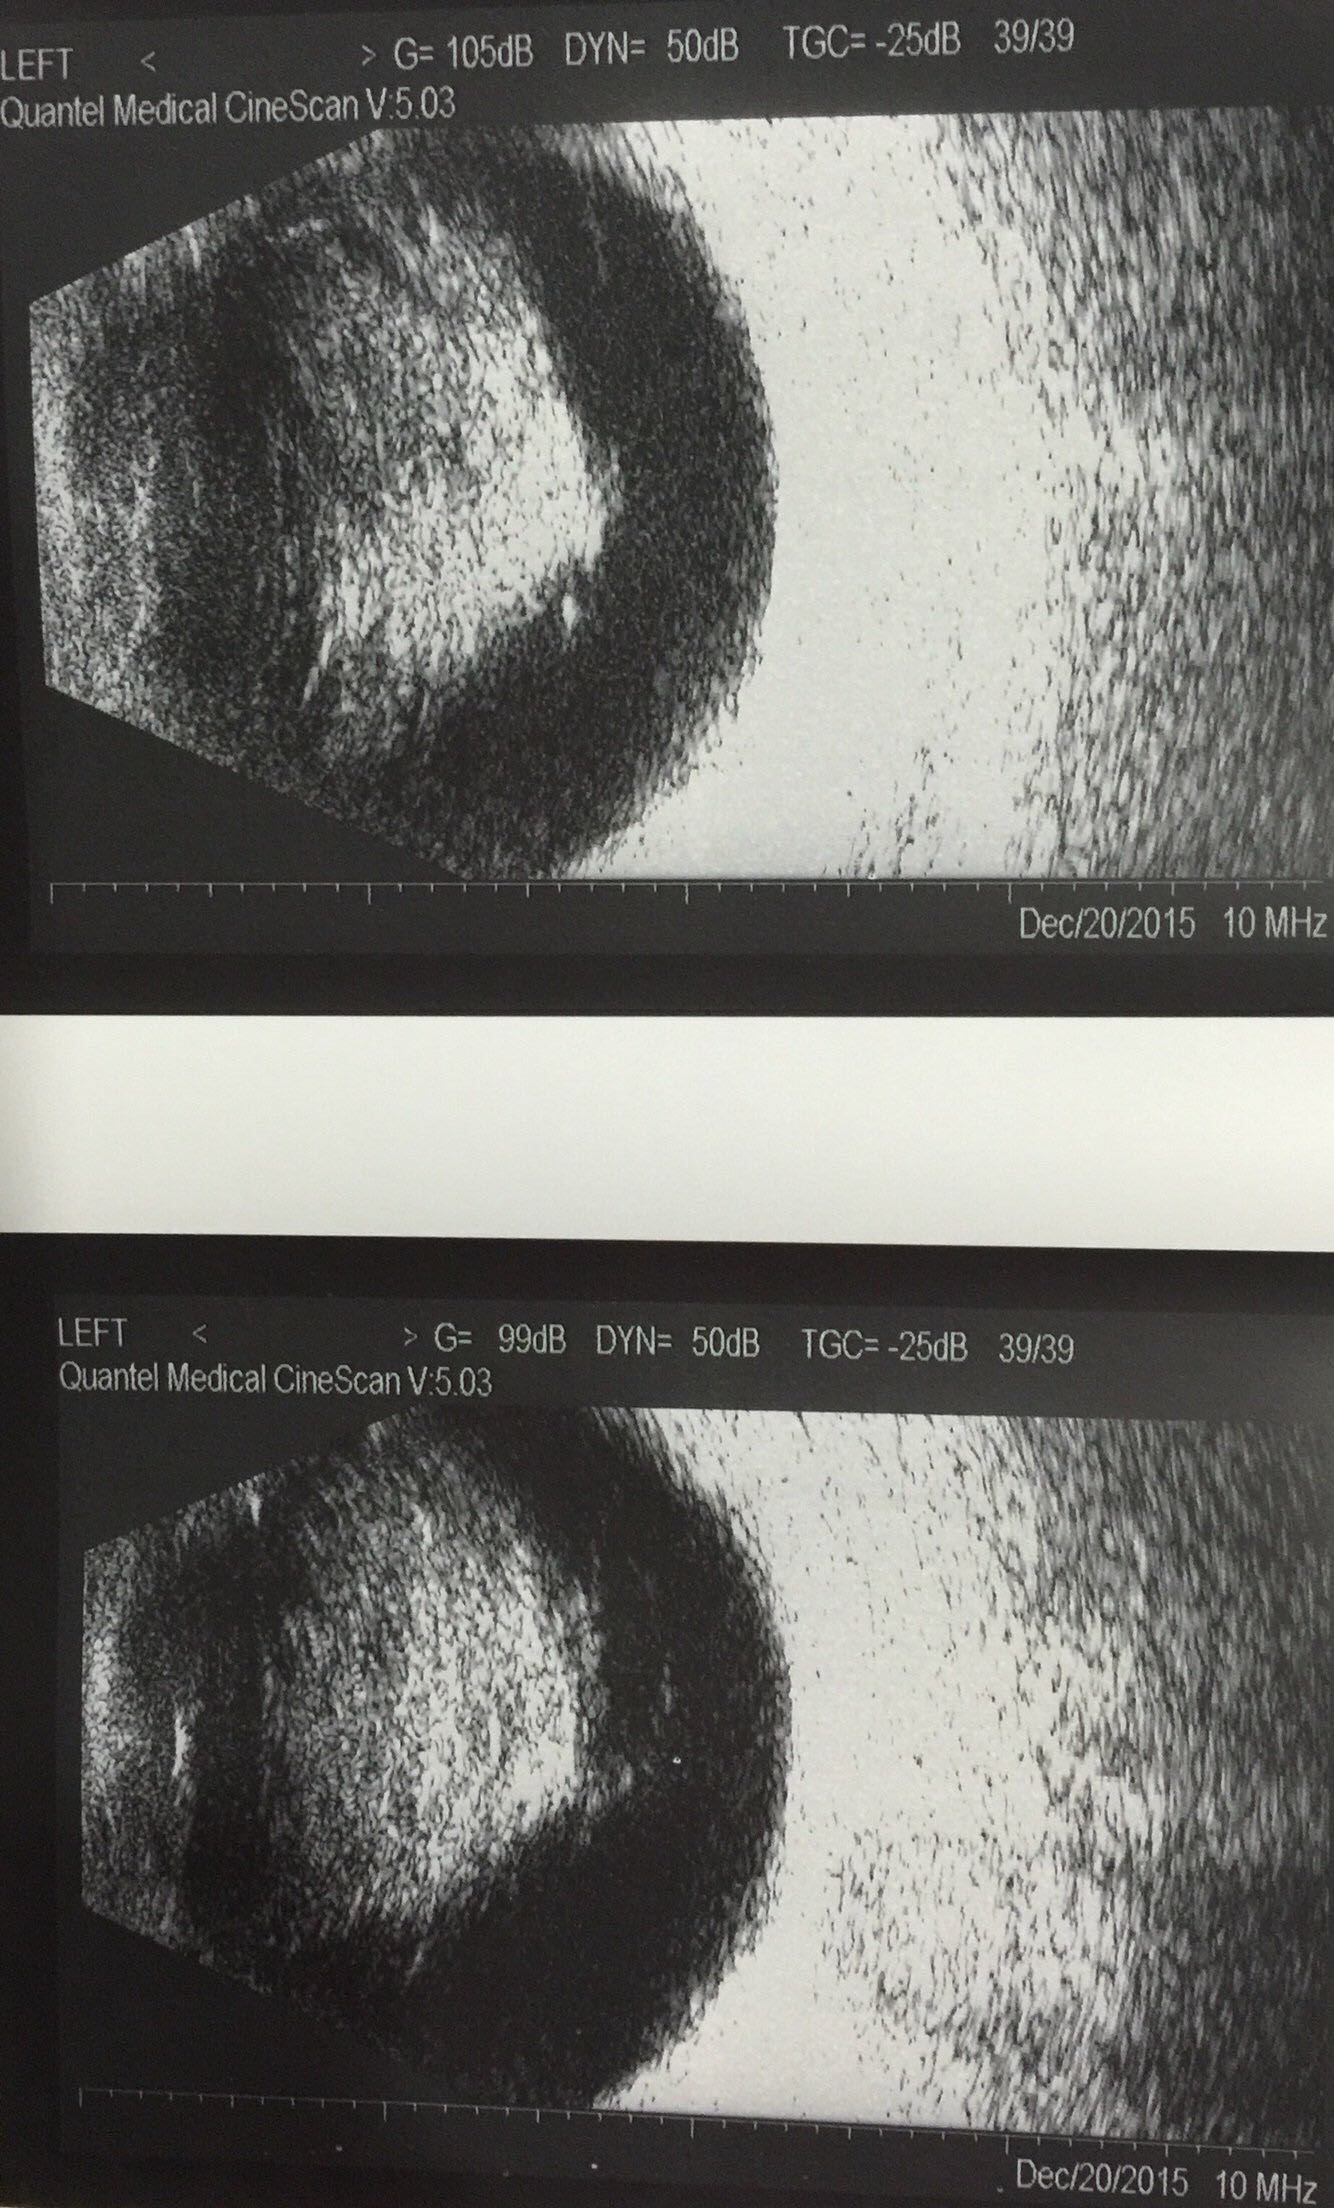

双眼星状玻璃体变性一例

张某,男,77岁,因 “双眼视力下降3个月”就诊。既往无特殊病史,无家族遗传史。

右眼视力0.6,左眼视力0.4,眼压右10.左11,双外眼无特殊,双眼晶体混浊,c0n2p1。双眼玻璃体眼底查体见图

双眼星状玻璃体变性,双眼白内障。

该患者左眼是否考虑行白内障联合微创玻璃体切除术?